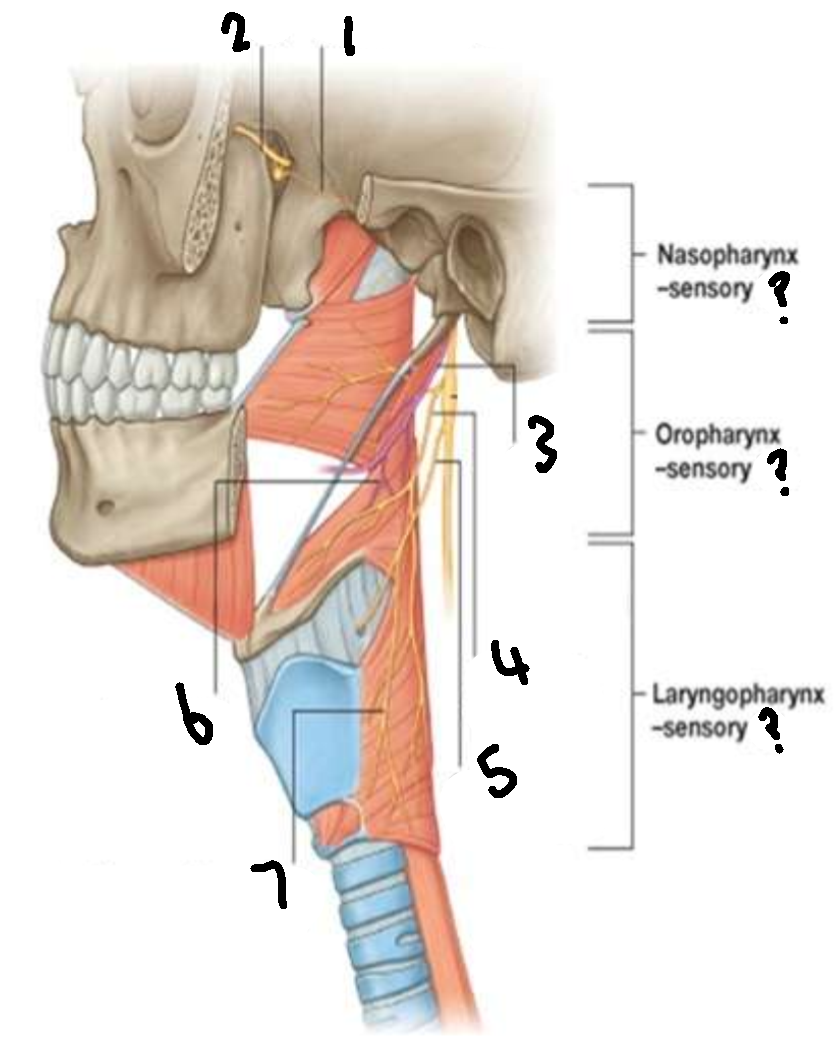

What provides sensory innervation to the nasopharynx?

mandibular branch of trigeminal V2

What provides sensory innervation to the oropharynx?

glossopharyngeal IX

What provides sensory innervation to the laryngopharynx?

vagus X

What is 1?

pharyngeal branch of V2

What is 2?

maxillary branch of trigeminal V2

What is 3?

glossopharyngeal IX

What is 4?

pharyngeal branch of vagus X

What is 5?

superior laryngeal nerve

What is 6?

pharyngeal branch of IX

What is 7?

external laryngeal branch of superior laryngeal nerve of X